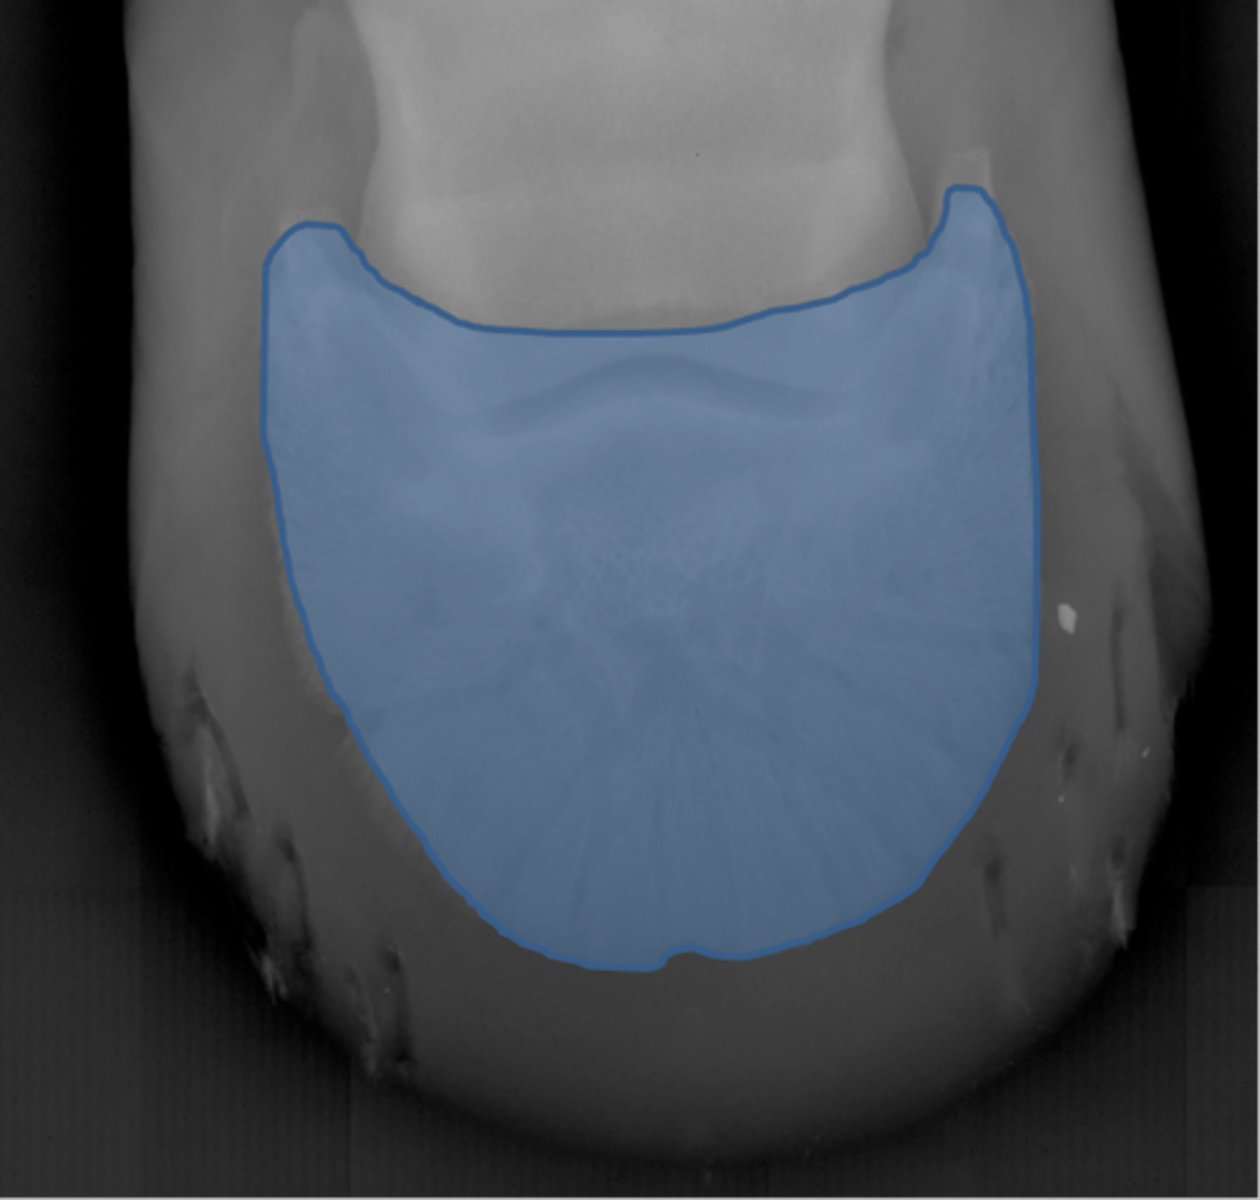

Coffin bone

Navicular bone

Crena

Vascular channelsv

Solar canal

Navicular bone

Flexor cortex

Navicular bone

Proximal border of navicular bone

Distal border of navicular bone

Synovial invaginations

Flexor skyline

What view is this?

1. Flexor surface

2. Corticomedullary distinction

3. Number of synovial invaginations

What is the flexor skyline used to evaluate?

Navicular bone

Articular surface of navicular bone

Flexor surface of navicular bone

Sagittal ridge

Synovial invaginations

Palmar process of P3

Palmar aspect of P2